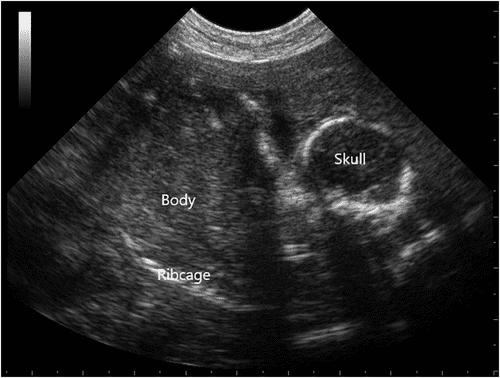

Наш ветеринар приедет на дом к питомцу, привезя с собой портативный аппарат УЗИ. Врач нанесет на живот собаки гель для ультразвукового сканирования. Это обеспечит хороший контакт между датчиком аппарата и кожей, что необходимо для получения четкого изображения. Ветеринар начинает сканировать живот питомца, перемещая датчик аппарата по различным участкам. Ориентируется на анатомические особенности, ищет признаки наличия плодов, изменения в структуре матки. Специалист внимательно изучает полученные изображения, определяет количество плодов, их размеры, положение, общее состояние. Ветеринар анализирует полученные изображения, делает заключение.

Если нет препятствий для посещения клиники, то УЗИ делают в специально оборудованном кабинете. Алгоритм процедуры не отличается от ее проведения в домашних условиях. Перед выполнением исследования питомцу может потребоваться легкая седация. Ветеринар проводит ультразвуковое исследование, перемещая датчик аппарата по животу суки для визуализации матки, плодов. Специалист оценивает состояние плодов, их количество, размеры, положение, а также общее здоровье, развитие. Ветеринар анализирует полученные изображения, делает заключение о состоянии суки. Он также выявляет любые аномалии, проблемы, связанные с вынашиванием потомства. После проведения УЗИ ветеринар консультирует владельца о результатах, предлагает рекомендации по уходу за животным, подготовке к родам.

При истинной беременности: УЗИ, проведенное после 20–25 дней после вязки, визуализирует плодные пузыри (на ранних сроках) и, что самое главное, сердцебиение эмбрионов. Наличие этих структур однозначно подтверждает, что сука беременна.

Что видно Мягкие ткани, плодные пузыри, пульсация сердца плодов, жидкость. Кости (скелеты плодов), их положение, размер и количество.

Диагноз: 5 живых эмбрионов, сердцебиение регистрируется у всех, средний срок — 48 дней. Плаценты и околоплодные пузыри без патологий. Матка не расширена, тонус в норме.

Что дало УЗИ: УЗИ позволило подтвердить жизнеспособность плодов, оценить их количество и положение, исключить мертворождение или кисты.